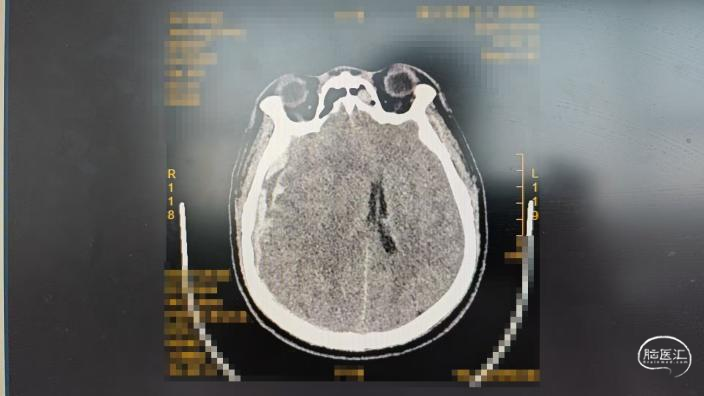

DC术前CT:

DC术后CT: